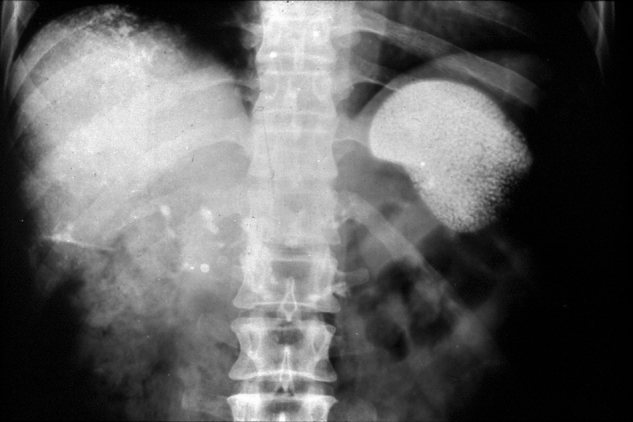

Da Thorium-232 und seine Folgeprodukte aufgrund der langen physikalischen und biologischen Halbwertszeiten lebenslang im menschlichen Körper deponiert werden, zeigten sich nach einer Latenzzeit von mehr als 15 Jahren zunehmend eine Reihe von vorwiegend stochastischen Spätschäden. Die Symptomatik wird allgemein pauschalisierend als „Thorotrastose“ bezeichnet. Bei der selektiven Anreicherung von Thorium-232 im Parenchym des retikuloendothelialen Systems, d.h. vor allem in Leber, Milz und Lymphknoten, waren Auswirkungen vor allem in diesen Organbereichen zu erwarten [16]. Abbildung 3, Abbildung 4

Abbildung 3.

Abdomenübersichtsaufnahme mit Thorotrast-Ablagerungen in Leber, Milz und abdominalen Lymphknoten.

Zur Untersuchung der Spätfolgen wurden mehre Studien unternommen. Die zwischen 1968 und 2016 durchgeführte, größte retrospektive deutsche Langzeit-Kohortenstudie umfasste 2326 Thorotrast-Patienten und -Patientinnen und 1890 Patienten und Patientinnen einer angepassten Kontrollgruppe. Mithilfe epidemiologischer Erhebungen sowie klinischer, radiologischer und biophysikalischer Untersuchungen wurden die Spätfolgen insbesondere in Bezug auf die Krebsentstehung untersucht. (Abbildung 1, Abbildung 2, Abbildung 3, Abbildung 4, Abbildung 5, Abbildung 6)